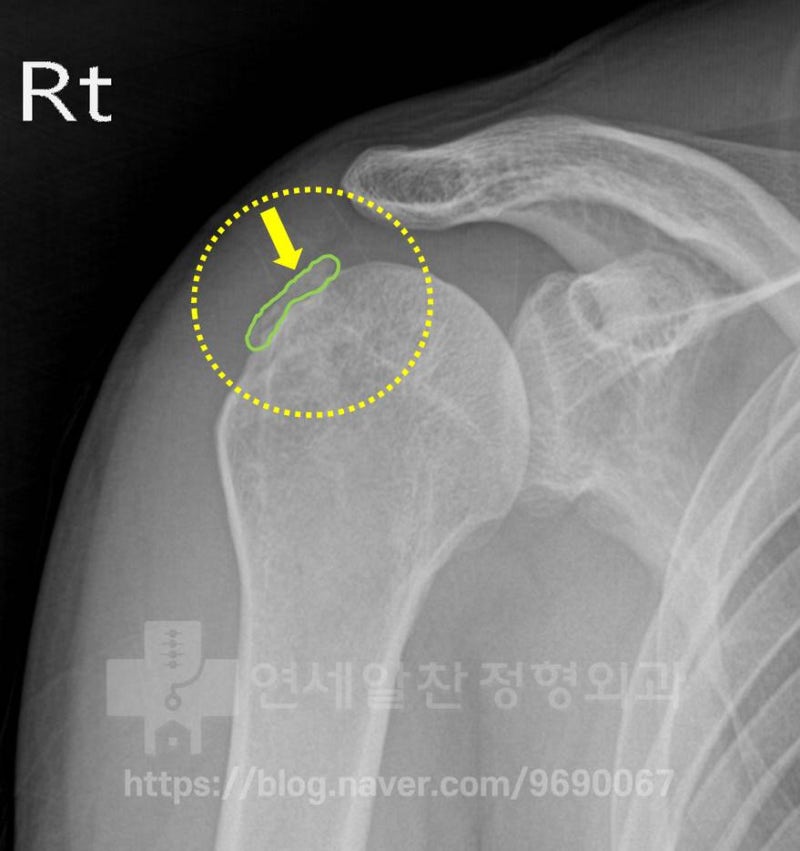

X-ray에서 보면 녹색선으로 표시된 부위에 석회처럼 보이는 것이 관찰됩니다. 또 다른 X-ray를 살펴보겠습니다.

노란색 점선으로 표시된 부위를 보면 상완골의 대결절 부위가 정상적이지 않고 뭔가 손상된 것 처럼 보입니다.